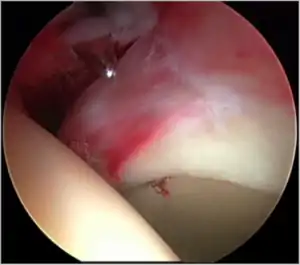

Cam-type femoroacetabular impingement

Cam impingement is created by the abnormal development of the femoral head-neck junction causing what has previously been described as a 'pistol-grip deformity'. This type of deformity is characterised by varying amounts of abnormal bone on the anterior and superior femoral neck at the head-neck junction (see fig. 6). The head-neck junction is at the base of the ball of the hip, where it joins the short neck, which in turn carries on downwards into the femur, or thighbone, itself. A bony protrusion or bump at the head-neck junction has been likened to a cam, an eccentric part of a rotating device. This leads to joint damage as a result of the non-spherical femoral head being forced into the acetabulum mainly with flexion and/or internal rotation. This may impart compression and shear forces to the articular cartilage, and may lead to labral tears and peeling away of the articular cartilage from the underlying bone, so-called cartilage delamination (see fig. 8).[9][10]

Standard arthroscopic treatment of symptomatic cam FAI involves debridement (resection) or repair of any labral [10] and chondral injuries [11] in the central compartment of the hip, and subsequent reshaping of the head-neck junction of the upper femur (osteochondroplasty) in the peripheral compartment [12][13] using high-speed motorised burrs that are similar in design to a dentist's drill (see fig. 9).